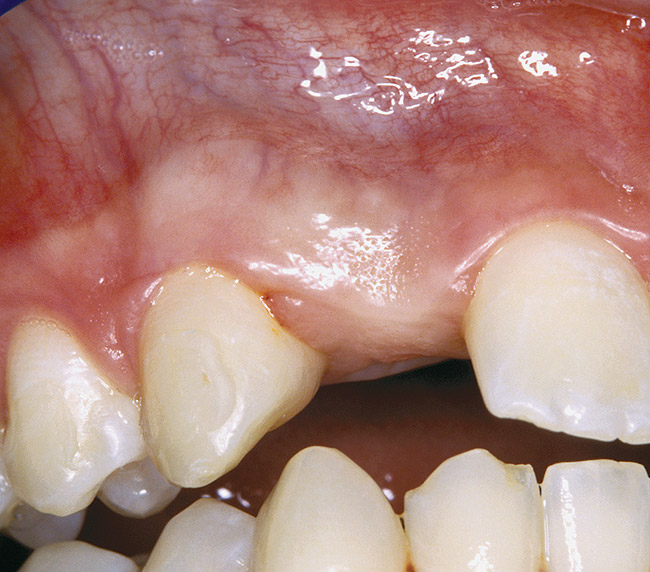

Periapical radiographs were taken to help determine the mesial-distal inclinations of the adjacent tooth roots (Figure 1). The radiographs revealed a serious issue, convergent roots for the right canine and right central, which eliminated that area as a potential implant-receptor site. The space between the left central and canine teeth was minimal, although the roots were relatively parallel. Clinical examination (manual palpation of the root eminences superiorly to the vestibule on the right side) confirmed the root convergence (Figure 2). The flat, wide zone of the keratinized tissue and lack of interdental papilla was evident for the missing right lateral incisor. There was a marked difference in clinical appearance for the left lateral, which could impact the eventual plan of treatment (Figure 3). Other significant clinical findings included bilateral facial bone concavities, which existed as a result of the congenitally missing tooth roots. As a diagnostic cue to the underlying bone topography, it is important to follow the demarcation between attached and unattached gingival tissue, and note the crestal width of the available keratinized tissue (Figure 4).

Figure 3  DIAGNOSTIC INFORMATION A difference in clinical appearance of the left lateral, buccal view.

Figure 3

Figure 4  DIAGNOSTIC INFORMATION Significant crestal width of keratinized tissue, buccal view.

Figure 4